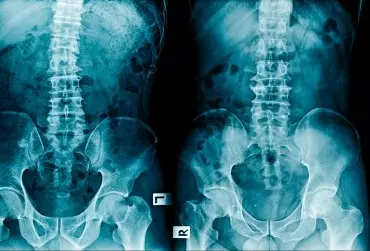

Iniekcje okołokręgowe pod kontrolą tomografii komputerowej z nawigacją laserową

W artykule zaprezentowano doświadczenia autora dotyczące wykorzystania tomografii komputerowej z nawigacją laserową w leczeniu zespołów bólowych odcinka lędźwiowego i stawu krzyżowo-biodrowego. Wykonywano iniekcje dodyskowe, okołostawowe i okołokorzeniowe z wykorzystaniem mieszaniny ozonu, leków steroidowych i miejscowych leków znieczulających, a także autologicznej surowicy własnej, tj. terapii Orthokine. Ze względu na bardzo wysoką skuteczność precyzyjnego pozycjonowania igły procedura odgrywa zasadniczą rolę w tzw. iniekcjach diagnostycznych u pacjentów na granicy leczenia operacyjnego.